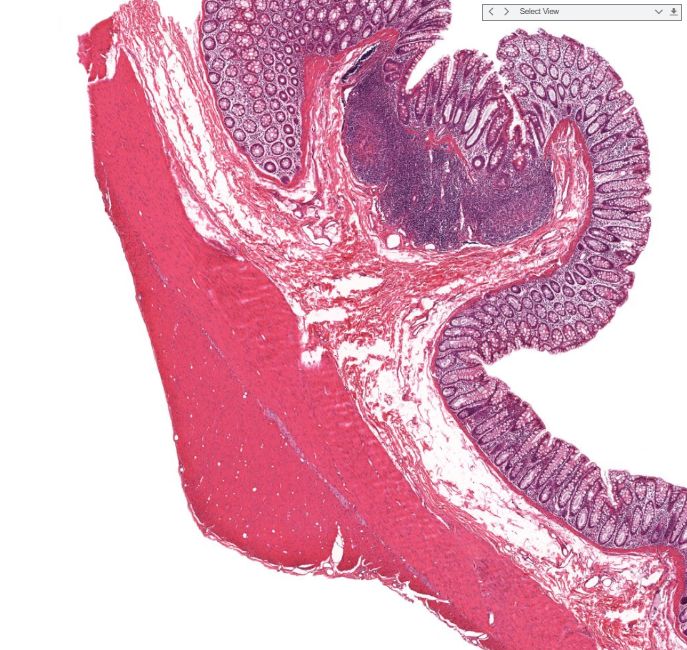

gastroesophageal junction

notice the shift from strat squamous to simple columnar (with long linear/coiled glands)